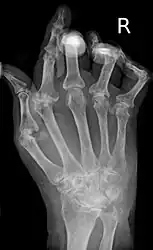

As the pathology progresses the inflammatory activity leads to tendon tethering and erosion and destruction of the joint surface, which impairs range of movement and leads to deformity. The fingers may suffer from almost any deformity depending on which joints are most involved. Specific deformities, which also occur in osteoarthritis, include ulnar deviation, boutonniere deformity (also "buttonhole deformity", flexion of proximal interphalangeal joint and extension of distal interphalangeal joint of the hand), swan neck deformity (hyperextension at proximal interphalangeal joint and flexion at distal interphalangeal joint) and "Z-thumb." "Z-thumb" or "Z-deformity" consists of hyperextension of the interphalangeal joint, fixed flexion and subluxation of the metacarpophalangeal joint and gives a "Z" appearance to the thumb.[19]: 1098 The hammer toe deformity may be seen. In the worst case, joints are known as arthritis mutilans due to the mutilating nature of the deformities.[23]

X-rays of the hands and feet are generally performed when many joints affected. In RA, there may be no changes in the early stages of the disease or the x-ray may show osteopenia near the joint, soft tissue swelling, and a smaller than normal joint space. As the disease advances, there may be bony erosions and subluxation. Other medical imaging techniques such as magnetic resonance imaging (MRI) and ultrasound are also used in RA.[23][56]

X-ray of the hand in rheumatoid arthritis. -